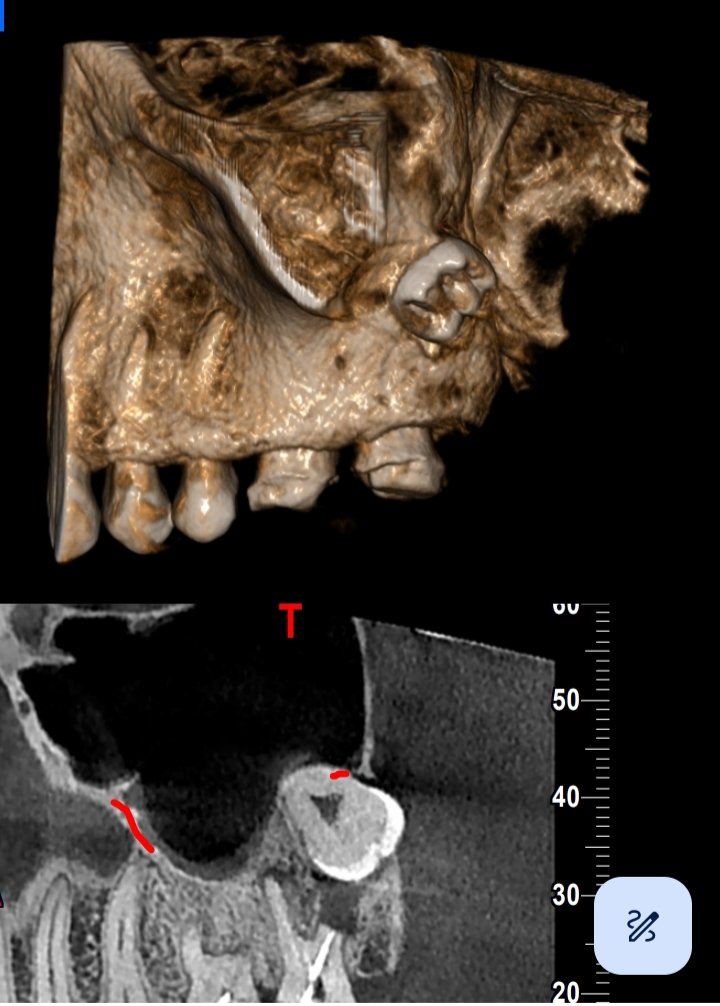

One of the primary applications of CBCT is in dentistry, where it plays a crucial role in various diagnostic and treatment planning processes. Dentists use CBCT scans to assess the condition of teeth, jawbones, and surrounding structures. It’s especially beneficial for visualizing complex anatomical features, such as the roots of teeth and the temporomandibular joint (TMJ).

In dental implant planning, CBCT helps dentists evaluate bone density and identify the optimal locations for implant placement. This detailed information contributes to more precise and successful implant surgeries. Additionally, CBCT aids in the diagnosis and treatment planning for conditions like impacted teeth, dental infections, and jaw disorders.

The advantages of CBCT extend beyond dentistry. In the field of maxillofacial imaging, CBCT is employed to assess conditions affecting the face and skull. This includes evaluating fractures, identifying tumors, and planning for corrective surgeries. CBCT’s ability to provide 3D reconstructions enhances the accuracy of surgical procedures, reducing potential risks and improving overall outcomes.